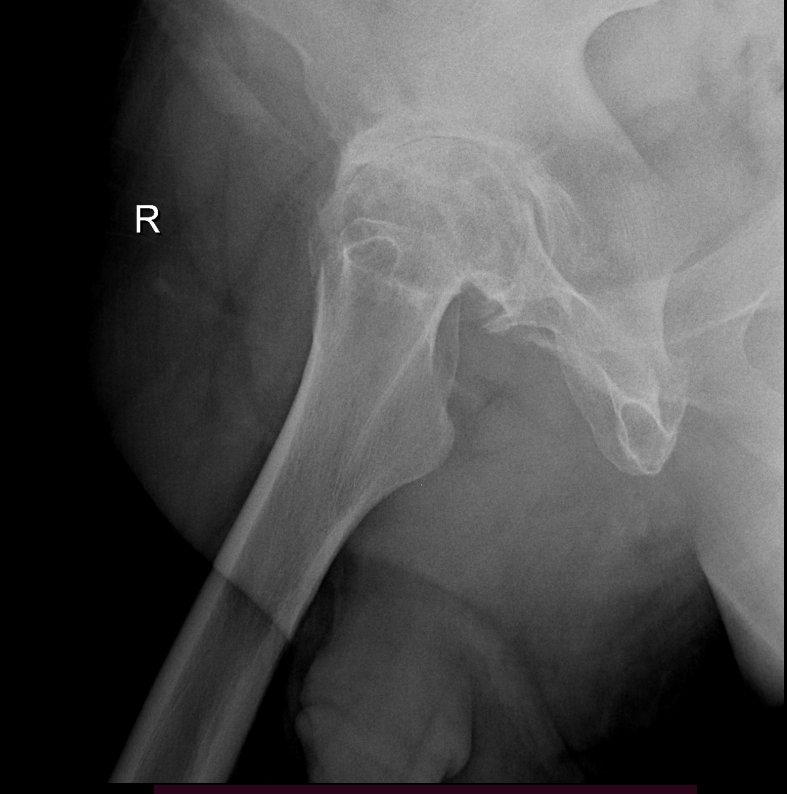

Arthritis is inflammation of the joints resulting in pain, swelling, stiffness and limited movement. Hip arthritis is a common cause of chronic hip pain and disability. The three most common types of arthritis that affect the hip are:

- Osteoarthritis: It is characterized by progressive wearing away of the cartilage of the joint. As the protective cartilage wears down, the bone ends rub against each other and cause pain in the hip. Rheumatoid arthritis: This is an autoimmune disease in which the tissue lining the joint (synovium) becomes inflamed, resulting in the production of excessive joint fluid (synovial fluid). This leads to loss of cartilage causing pain and stiffness.

- Traumatic arthritis: This is a type of arthritis resulting from a hip injury or fracture. Such injuries can damage the cartilage and cause hip pain and stiffness over a period of time.

The most common symptom of hip arthritis is joint pain and stiffness resulting in limited range of motion. Vigorous activity can increase the pain and stiffness which may cause limping while walking.

Diagnosis is made by evaluating medical history, physical examination and X-rays.